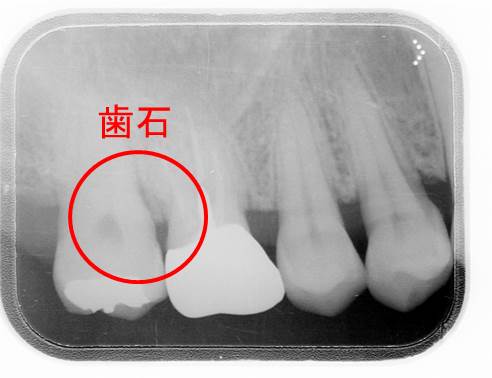

歯石発見ヽ(´Д`;≡;´Д`)丿

これは歯周ポケットの中です。

当然、歯ブラシは全く届きません。

(参考写真)